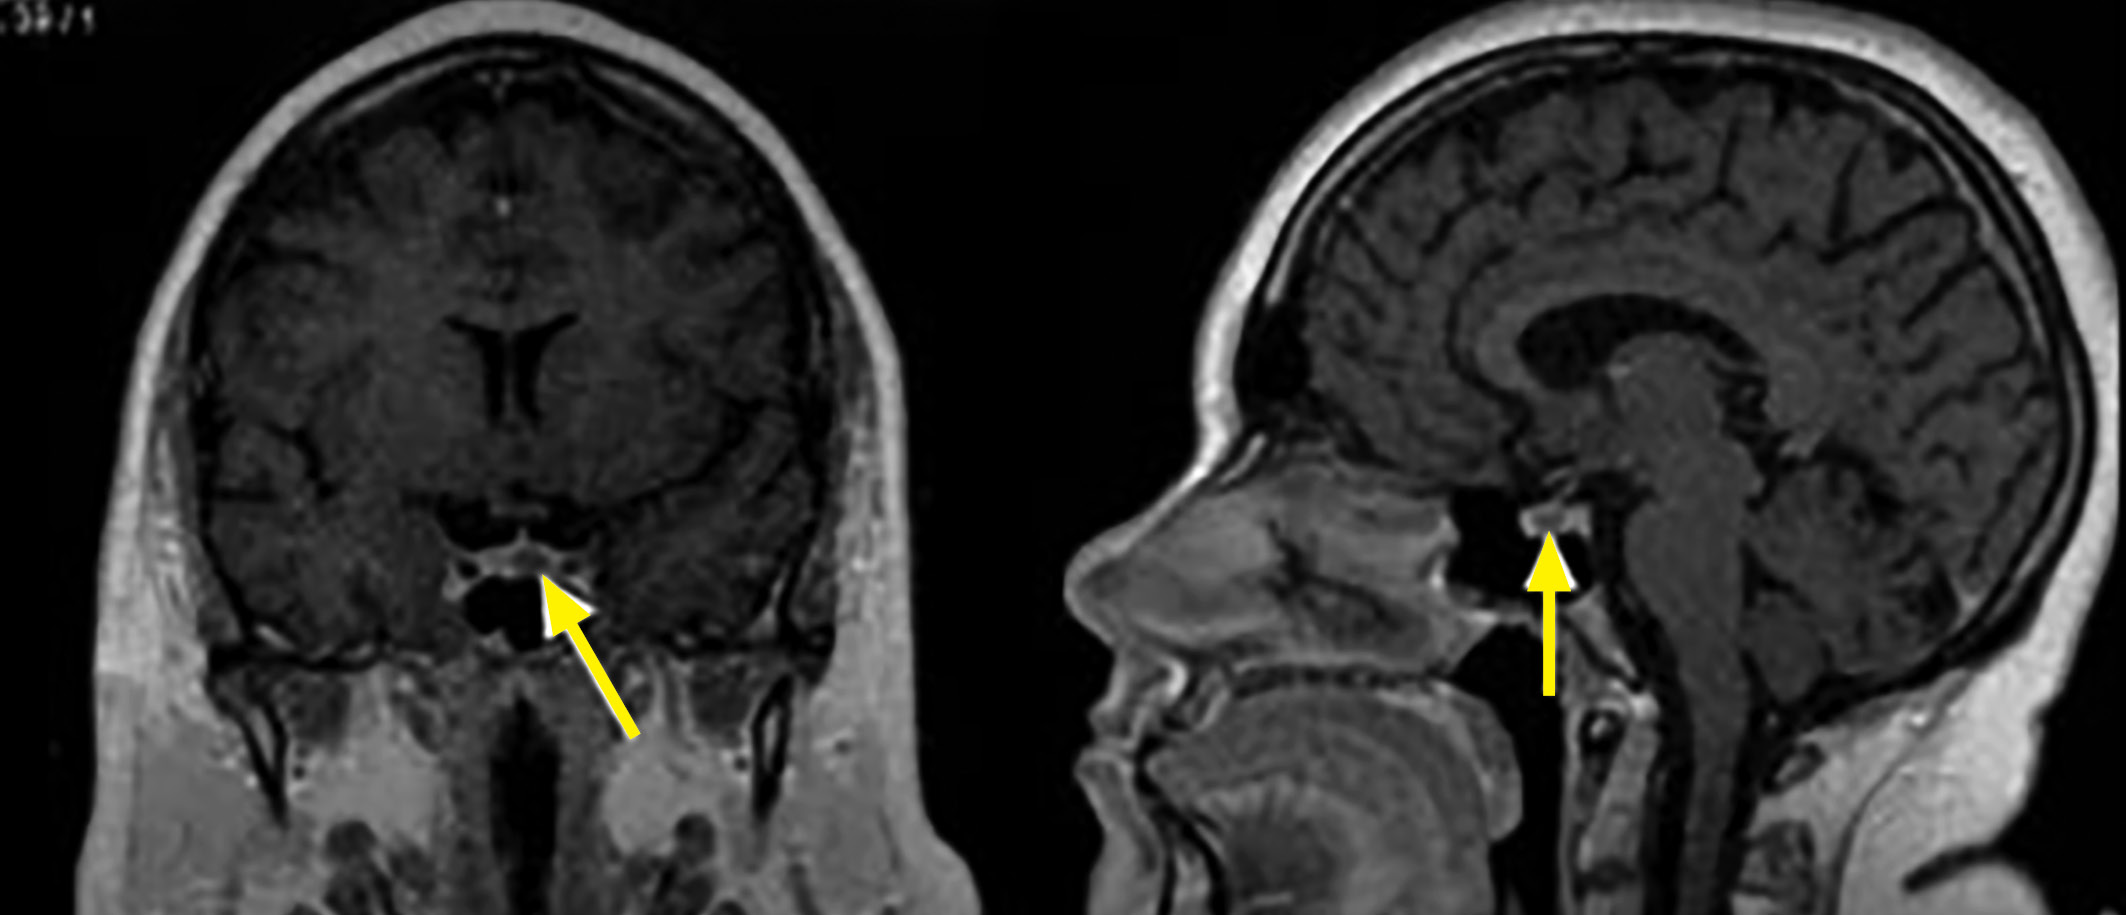

На МРТ микроаденомы в большинстве случаев имеют гипоинтенсивный сигнал в Т1-взвешенном режиме, реже изоинтенсивный. В случае микроаденом гиперинтенсивный сигнал в Т1-режиме может свидетельствовать о кровоизлиянии в опухоль, что более характерно при пролактиномах. В Т2-взвешенном режиме интенсивность сигнала различна и может быть от гиперинтенсивного до гипоинтенсивного. При введении контрастного вещества характерно значительно менее интенсивное накопление его опухолью по сравнению с нормальной тканью гипофиза.

Рисунок 6. Эндоселлярная кортикотропинома. На фронтальных МР-томограммах в Т1-взвешенном режиме выявляется гипоинтенсивная опухоль (стрелка).

Рисунок 7. Эндоселлярная кортикотропинома. На фронтальных (А) и сагиттальных (Б) МР-томограммах в Т1-взвешенном режиме при введении контрастного вещества отмечается сниженное накопление контрастного вещества, в отличие от нормальной ткани гипофиза.